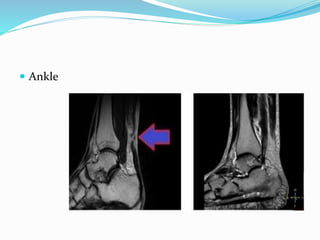

 Ankle